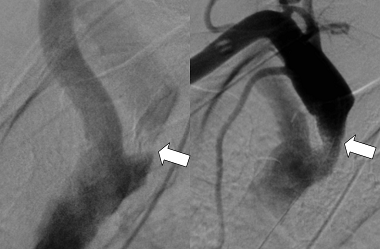

図の説明

左 矢印の部分の血管が狭窄しています。

右 ステントを留置して血流が改善しました(矢印)。